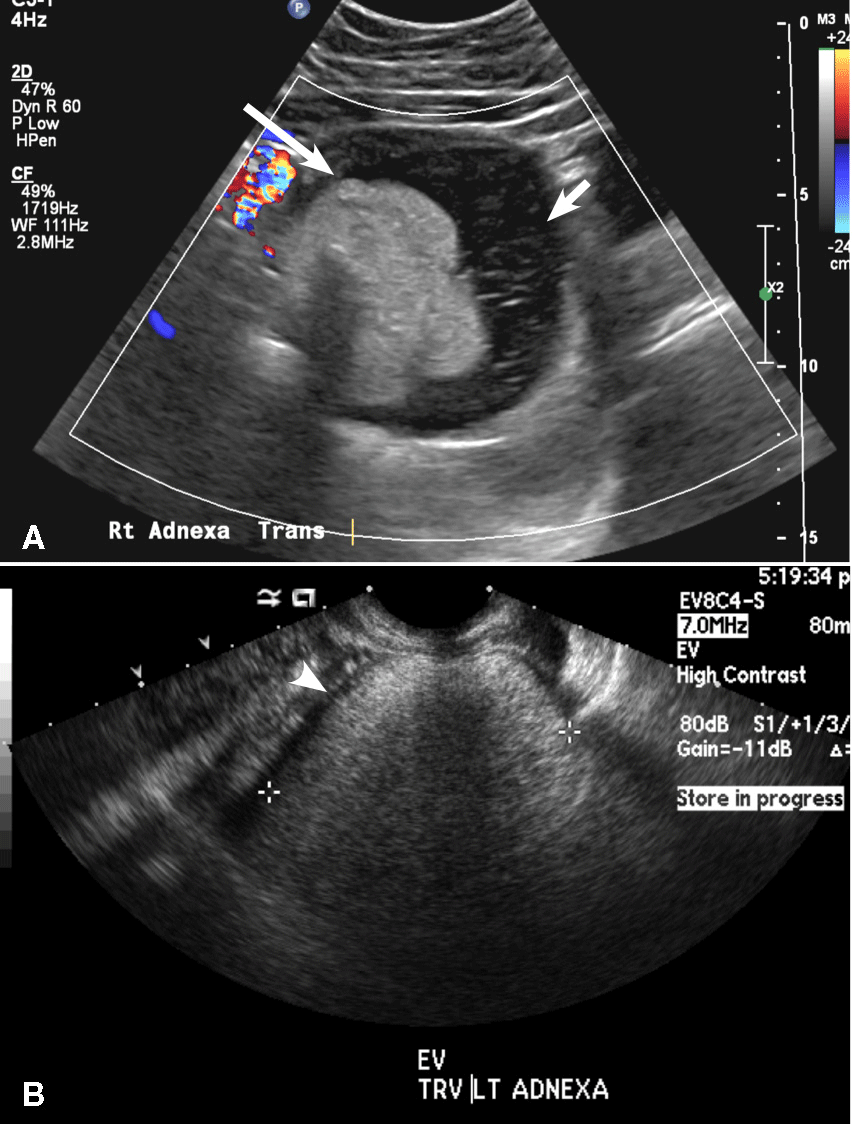

(D) Dermoid INCORRECT

This common benign ovarian tumor has varying appearances. The most common appearance is a cystic lesion with a focal echogenic nodule (long arrow) protruding into the cyst (Rokitansky nodule).2 The second most common appearance is a focal or diffuse hyperechoic mass with areas of acoustic shadowing (arrowhead) from the sebaceous material and hair (tip of the iceberg sign). A third common appearance is a cystic lesion with multiple thin echogenic bands (lines and dots), which are hair floating within the cyst (short arrow). There is no internal vascular flow identified.

Dermoid cysts. (A) Transvaginal pelvic ultrasound of the right adnexa demonstrates a cystic lesion with a focal echogenic nodule protruding into the cyst compatible with a Rokitansky nodule (long arrow). Also seen are multiple thin echogenic lines and dots (short arrow). (B) Transvaginal pelvic ultrasound of the left adnexa shows a diffuse hyperechoic mass with areas of acoustic shadowing (arrowhead) from the sebaceous material and hair (tip of the iceberg sign).